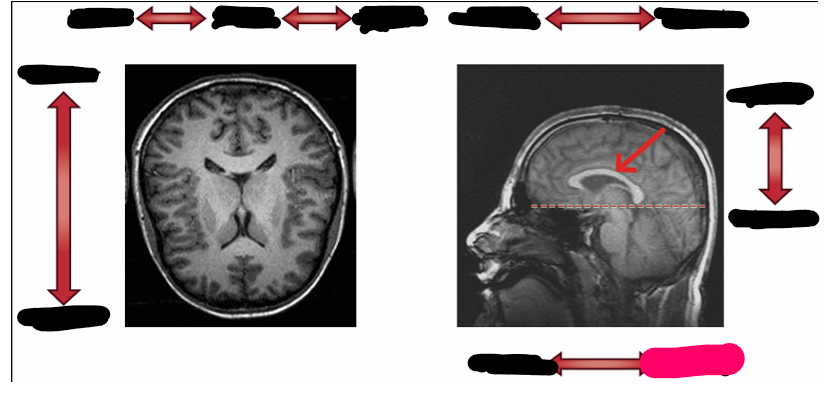

sagittal

horizontal/ transverse

coronal

dorsal

ventral

corpus callosum

central fissure

brocas area

sylvian fissure

supplementary motor area

primary motor cortex

primary somatosensory cortex